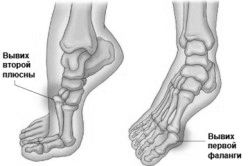

Досить поширена травма - вивих стопи, від неї ніхто не застрахований. Особливо часто страждають спортсмени і літні люди. Це може статися через різку навантаження на кісточку (при бігу і стрибках). У таких випадках кістка виштовхується з суглоба, що може привести до розтягування або розриву зв'язок. Що потрібно робити при вивиху стопи?

Залежно від ступеня серйозності розрізняють наступні форми вивиху:

- розтягнення зв'язки (легка),

- частковий розрив зв'язки (середня),

- повний розрив зв'язки (важка).